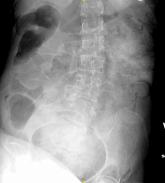

Emergency Imaging: Severe Chronic Abdominal Pain

An otherwise healthy 20-year-old

woman presented for evaluation

of severe chronic abdominal pain.